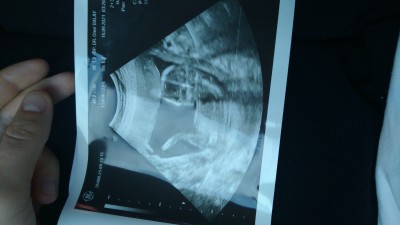

kizlar cinsiyet için kara lahana testi yaptım yapan varsa söyleyebilir mi 17 haftalık oldum hala göstermiyor çok merak ediyorum şuraya ultrasonuda ilistireyim :)